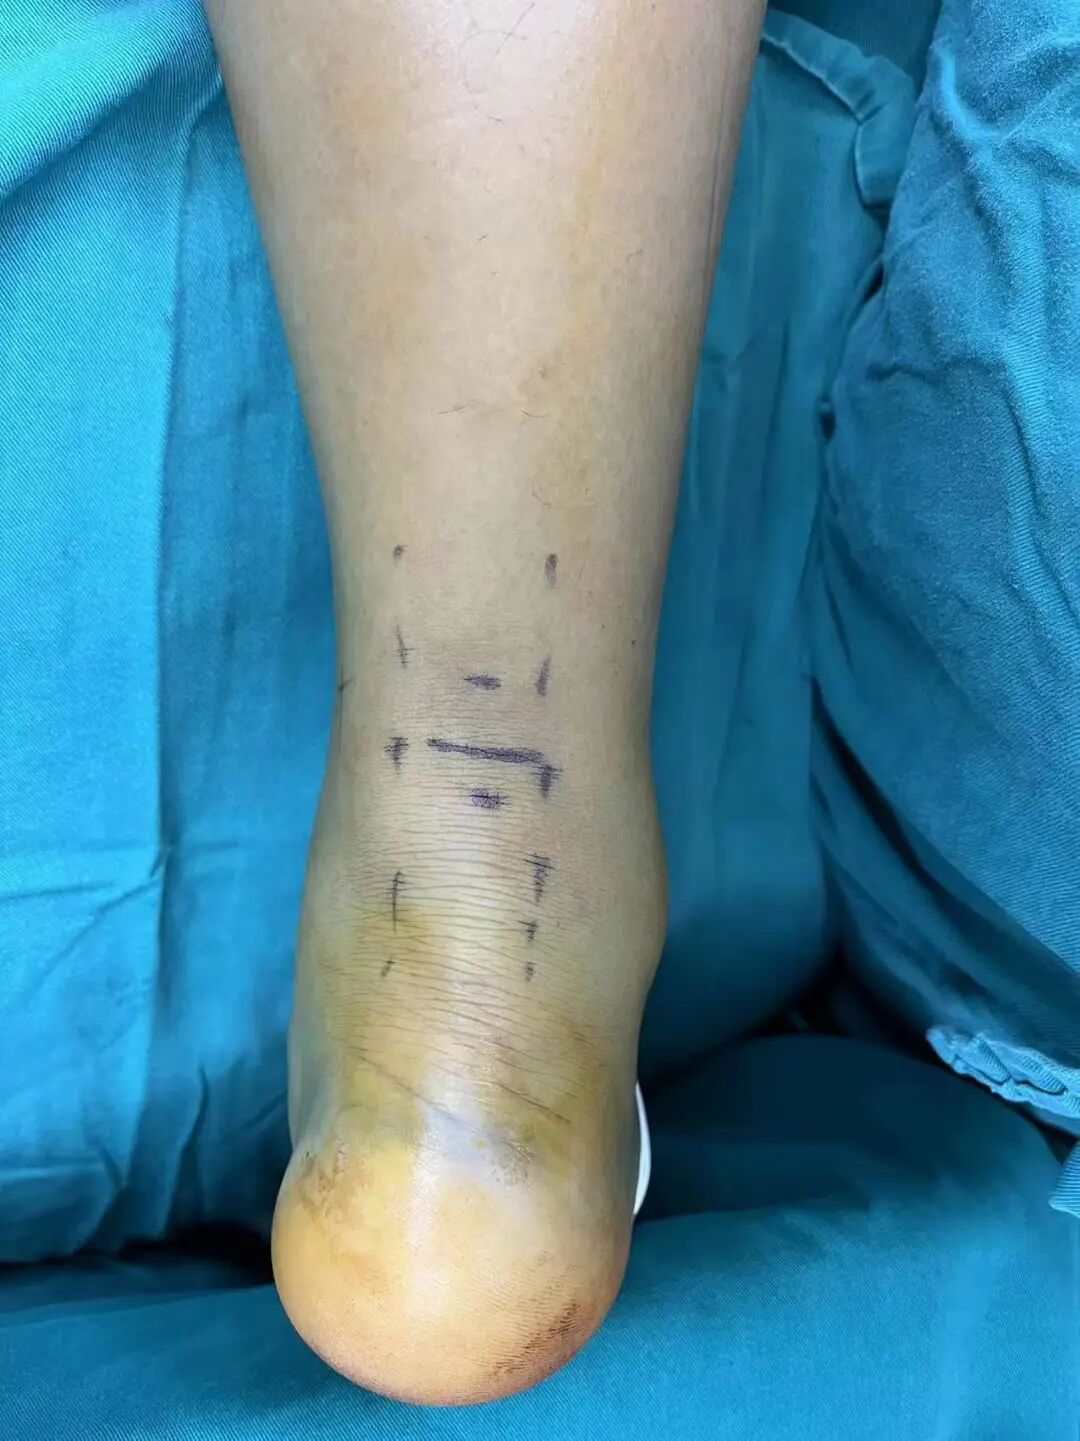

案例1:患者男性,39岁,因“弹跳后出现右足跟肿痛、右踝活动受限1天”入院,查体:右下肢跛行,右足跟后侧局部肿胀,淤血青紫,跟腱处凹陷,压痛,右跟腱后侧空虚,右踝关节主动背伸活动不能,被动活动好,Thompson征阳性。